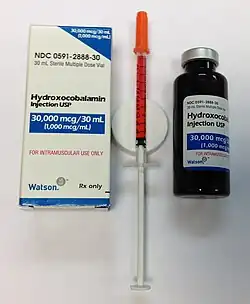

Because pernicious anemia is due to a lack of intrinsic factor, it is not preventable.[11] Pernicious anemia can be treated with injections of vitamin B12.[7] If the symptoms are serious, frequent injections are typically recommended initially.[7] There are not enough studies that pills are effective in improving or eliminating symptoms.[12] Often, treatment may be needed for life.[13]

Pernicious anemia is usually easily treated by providing the necessary level of vitamin B12 supplementation.[63] Pernicious anemia can be treated with intramuscular injections of vitamin B12.[64] Initially in high daily doses, followed by less frequent lower doses, as the condition improves.[64] Activity may need to be limited during the course of treatment.[7] As long as the body is saturated with vitamin B12 expected to result in cessation of anemia-related symptoms and there are no other symptoms, unless there are irreversible neurological complications.[63] There are not enough studies on whether pills are as effective in improving or eliminating symptoms as parenteral treatment.[12] Folate supplementation may affect the course and treatment of pernicious anemia if vitamin B12 not replaced.[65] In some severe cases of anemia, a blood transfusion may be needed to resolve haematological effects.[5] Treatment is lifelong.[5][66]

The treatment of PA varies by country and area. Opinions vary over the efficacy of administration (parenteral/oral), the amount and time interval of the doses, or the forms of vitamin B12 (e.g. cyanocobalamin/hydroxocobalamin). More comprehensive studies are still needed in order to validate the feasibility of a particular therapeutic method for PA in clinical practices.

Understanding of the pathogenesis of pernicious anaemia increased over subsequent decades. It had long been known that the disease was associated with defects in the gastrointestinal tract: patients had chronic gastritis and lack of acid secretion (achlorhydria). It is known that transport of physiological amounts of vitamin B12 depends on the combined actions of gastric, ileal and pancreatic components. The gastric moiety was discovered and named 'intrinsic factor' by William Castle in 1930. A further important advance was made in the early 1960s by Doniach with the recognition that pernicious anemia is an autoimmune disease.[71] Pernicious anemia is eventually treated with only injections of B12; injections are typically 1 mg every other day, or twice weekly.